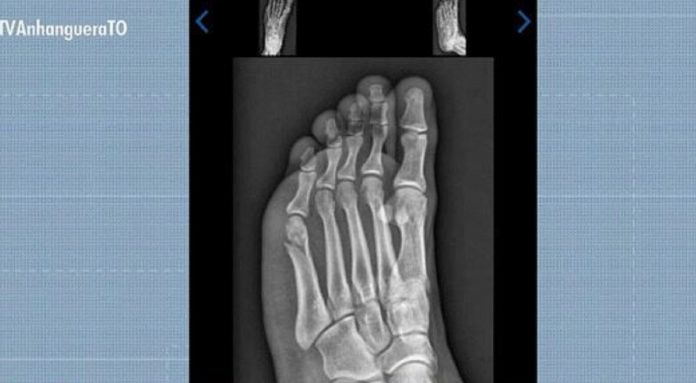

Concurseiro concluiu prova de corrida do TAF com fratura no pé

Reprodução/TV Anhanguera